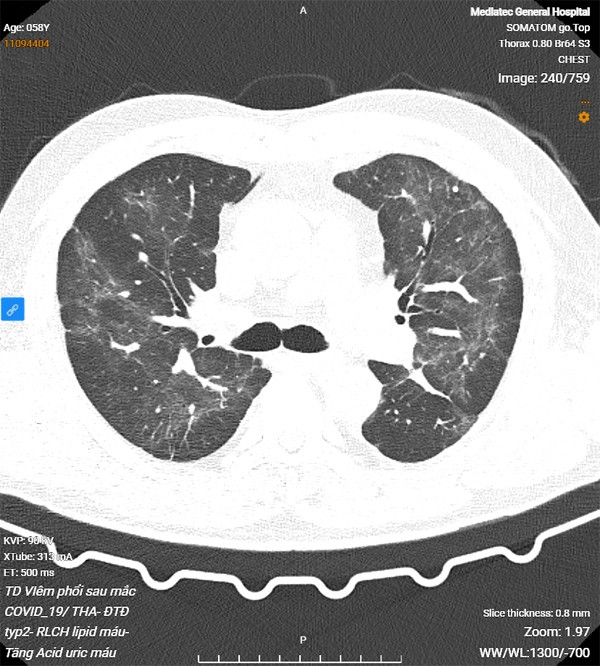

Tại thời điểm khám, BN có mệt, khó thở, hụt hơi nhất là khi gắng sức, ho nhiều và có đờm trắng; thăm khám thấy thông khí giảm. Sau thăm khám đầu vào, bệnh nhân được chụp CT phổi và làm các xét nghiệm đánh giá tình trạng tim mạch, tiểu đường cũng như toàn trạng của cơ thể.

Kết quả CT phổi có hình ảnh tổn thương kính mờ, dày tổ chức kẽ và dải xơ dưới màng phổi hai bên, hướng đến tổn thương hậu Covid-19. Đo chức năng hô hấp thấy giảm lưu lượng các nhánh phế quản vừa và nhỏ.